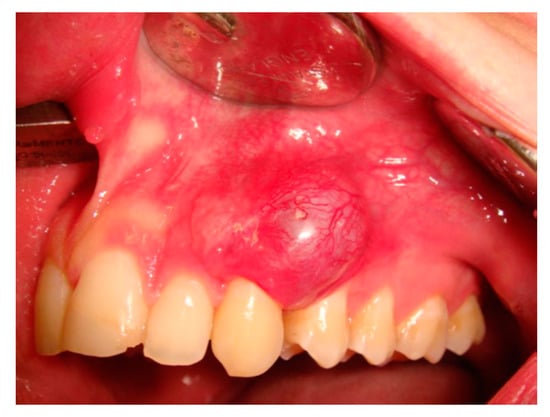

2. Case Presentation